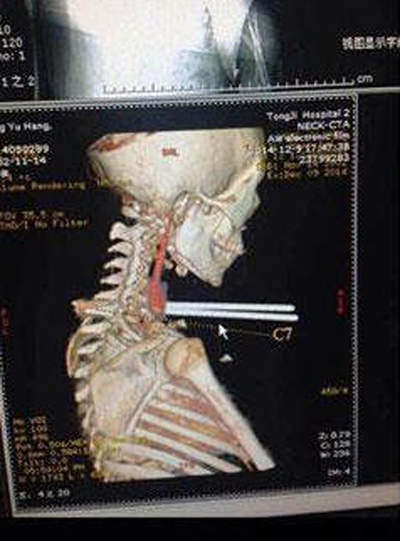

Bé trai bị đũa đâm vào cổ.

Nhưng khi Jun đang chạy ở sân trường, một phụ huynh của học sinh cùng lớp va vào cậu. Cú va chạm khiến Jun ngă về phía trước và hai đũa cắm vào cổ của em. Ngay lập tức, nhân viên bảo vệ và giáo viên trong trường gọi xe cứu thương để đưa Jun tới bệnh viện.

Tại bệnh viện, các bác sĩ sửng sốt khi kết quả siêu âm cho thấy đôi đũa không gây nên bất kỳ tổn thương nào cho các cơ quan nội tạng.

"Đôi đũa không đâm trúng khí quản, thực quản và các mạch máu chính của nạn nhân. Cậy ấy rất may mắn. Sau đó chúng tôi đă phẫu thuật để lấy đôi đũa", Zhou Jen, một bác sĩ, kể.

H́nh ảnh bé trai bị đũa đâm vào cổ khi bác sỹ chụp.

Zhou nói thêm rằng đôi đũa được làm bằng thép chứ không phải gỗ, nên nguy cơ biến chứng do nhiễm trùng từ vết thương rất thấp. Các bác sĩ đang theo dơi sức khỏe của Jun và em có thể về nhà trong vài ngày tới.